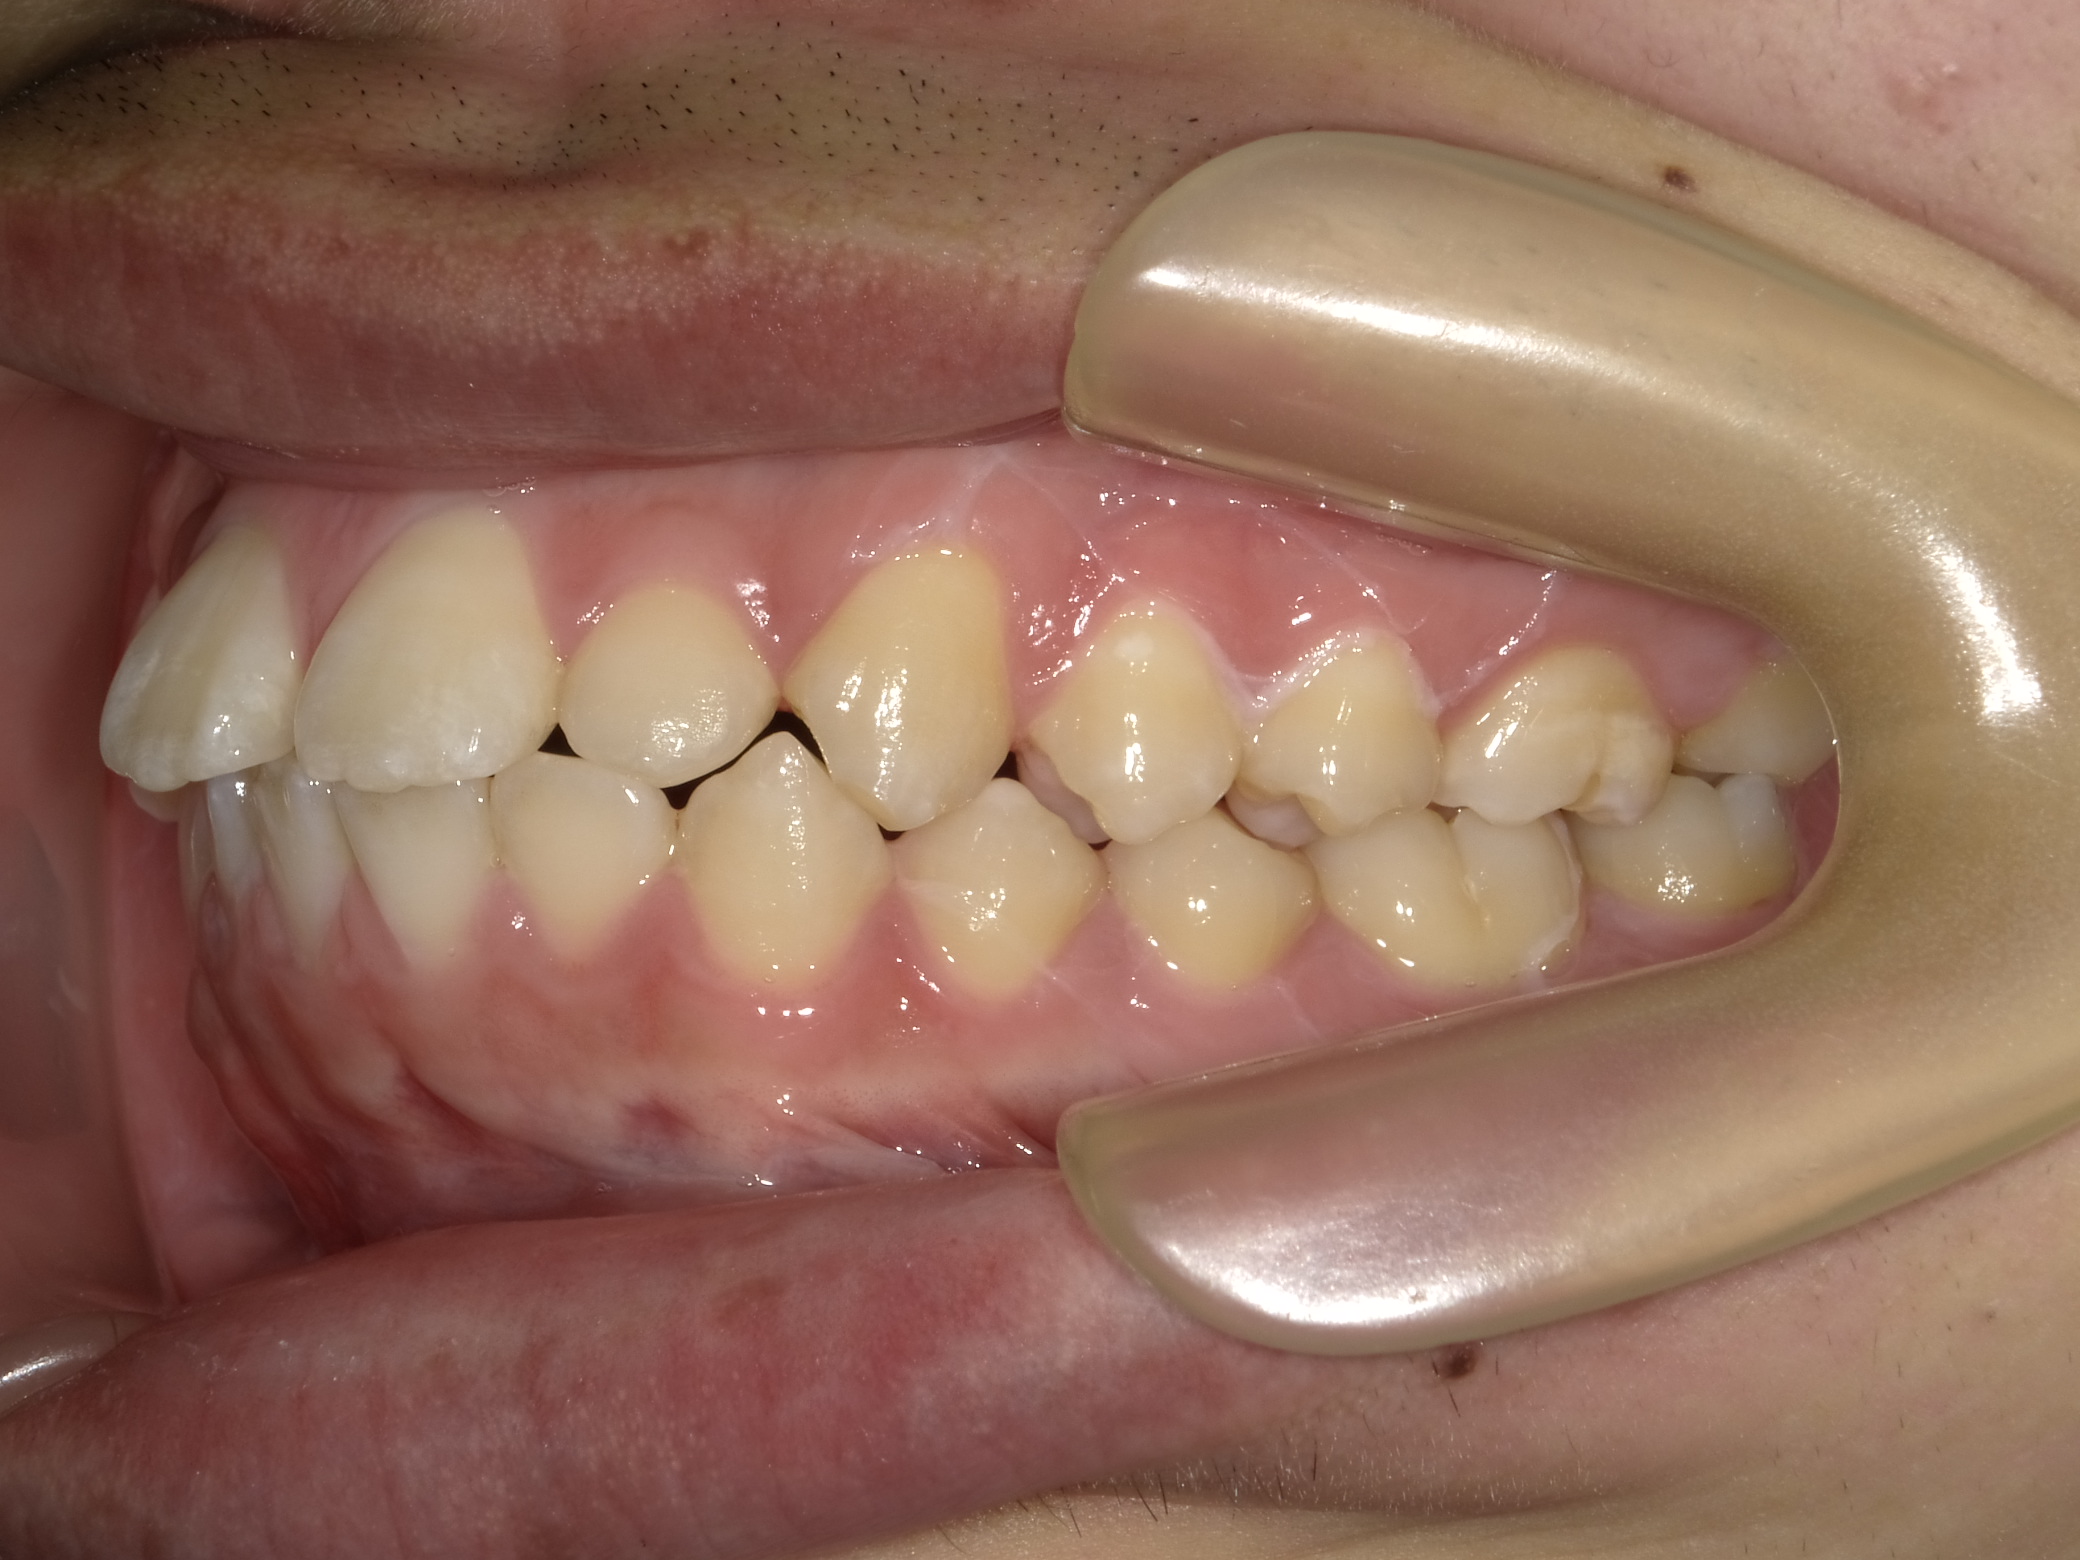

| 症例分類 | 上下顎前突 |

|---|---|

| 主訴 | 前歯が出ていて、口が閉じにくい |

| 年齢 | 20歳0ヶ月 |

| 性別 | 男性 |

| 抜歯部位 | 上下顎両側第一小臼歯 |

| 使用装置 | 歯の表側からのマルチブラケットによる矯正装置 |

| 治療期間 | 2年10ヶ月 |

| 保定装置 | 取り外し式保定装置 |

| 費用 | 相談料0円、検査料55,000円 動的矯正治療費935,000円 調整料6,600円×28回分 保定装置料0円 |

| リスク・注意点 | 上下の個々の歯の大きさに対して上下の顎が小さく歯が並ぶスペースが不足したために上下の前歯が前方に傾斜して、上下顎前突が生じています。これらを改善するために、上下顎両側第一小臼歯を抜歯して、このスペースを用いて歯を排列しました。歯の動き方には個人差があり、予想された治療期間が延長する可能性があります。 治療中は矯正歯科装置が歯の表面に付いており、歯が磨きにくくなるため、むし歯や歯周病が生じるリスクが高まります。ハミガキを適切に行ってお口の中を常に清潔に保ち、さらに、かかりつけ歯科医に定期的に受診することが大切です。 顎間ゴムの使用状況、定期的な通院など、矯正歯科治療には患者さんの協力が必要であり、それらが治療結果や治療期間に影響します。 治療の経過によっては当初予定していた治療計画を変更する可能性があります。 歯を動かすことにより歯根が吸収することがあります。 保定装置の装着時間が十分確保できない場合、歯並びや、咬み合せの「後戻り」が生じる可能性があります。 |